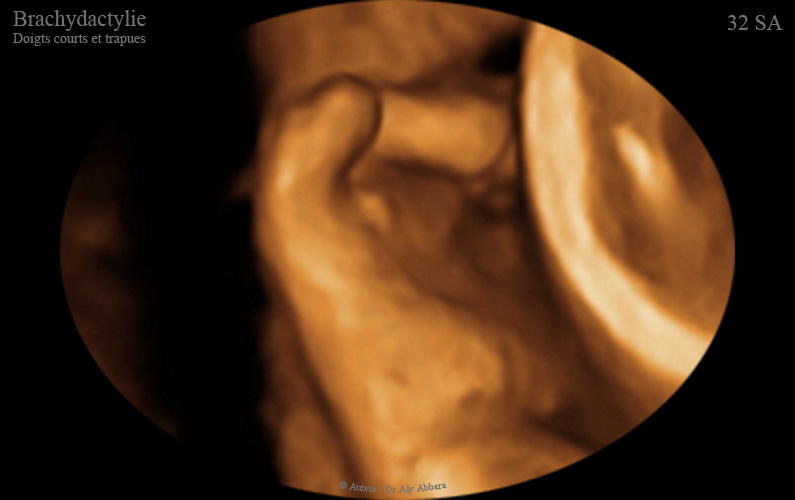

Images échographiques en 2D et en 3D montrant l'aspect ultra-sonre d'une brachydactylie : doigts courts et également trapues (larges et courts.

Ce signe fait partie des anomalies mineures parfois retrouvées en cas de trisomie 21 (comme c'est la situation, dans le cas présenté dans cet article).

• Dans la trisomie 21, les mains peuvent être trapues (courte et larges).